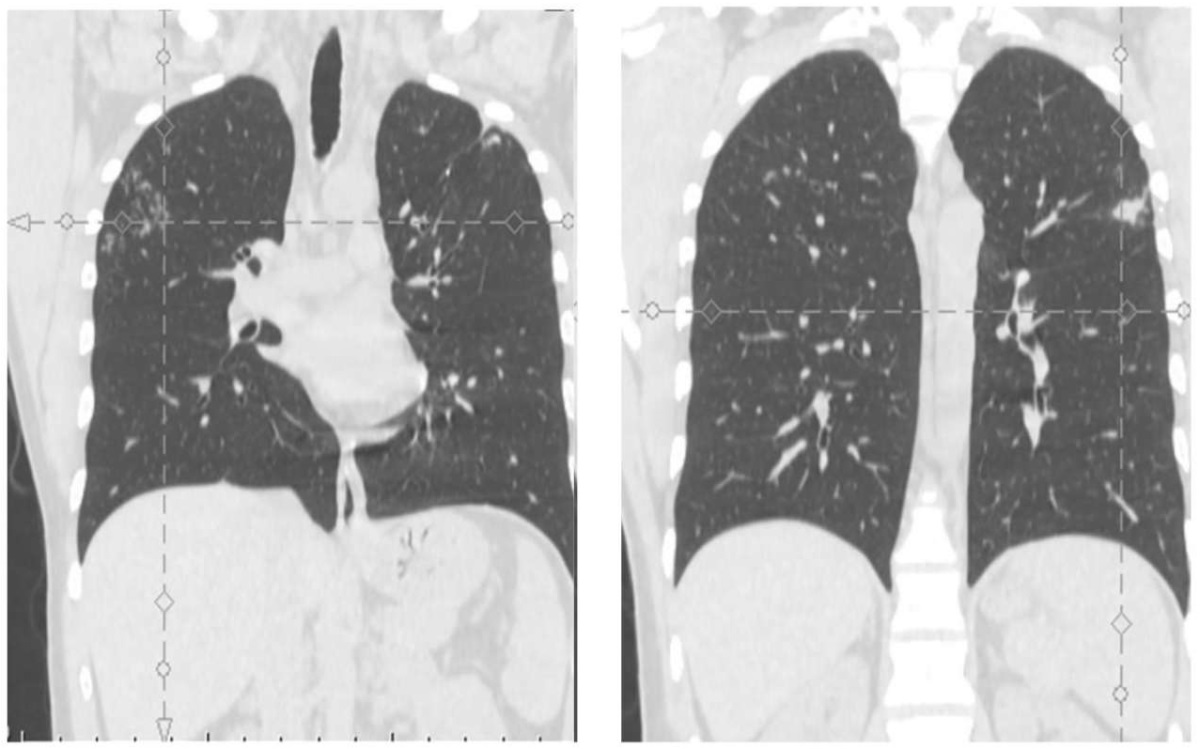

Из анамнеза: по результатам флюорографического исследования, выполненного в июле 2022 г. при медицинском осмотре, у пациента заподозрен туберкулез легких, в связи с этим он направлен на дополнительное обследование. В НПЦ «Фтизиатрия» проведена компьютерная томография органов грудной клетки (рис. 1), выявлены очаговые изменения специфического характера в сегментах S1–2 обоих легких. Пациент был госпитализирован для проведения химиотерапии туберкулеза.

Рис. 1. Компьютерная томограмма органов грудной клетки пациента О. от 05.07.2022, до начала лечения

Fig. 1. Computed tomography scan of the chest: Patient О., 5 July 2022, before treatment